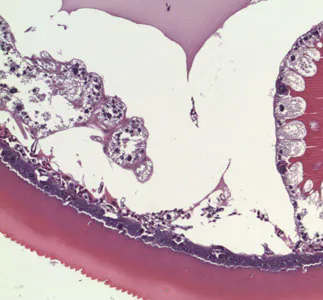

An 81-year-old man, with a previous history of basal-cell carcinoma on his upper right arm and shoulder, presented with a small protuberance in the hollow of his left knee. A biopsy specimen was collected, sectioned, and stained with hematoxylin-and-eosin (H&E). Figures A–D show what was observed by the attending pathologist. What is your diagnosis? Based on what criteria?

Figure C